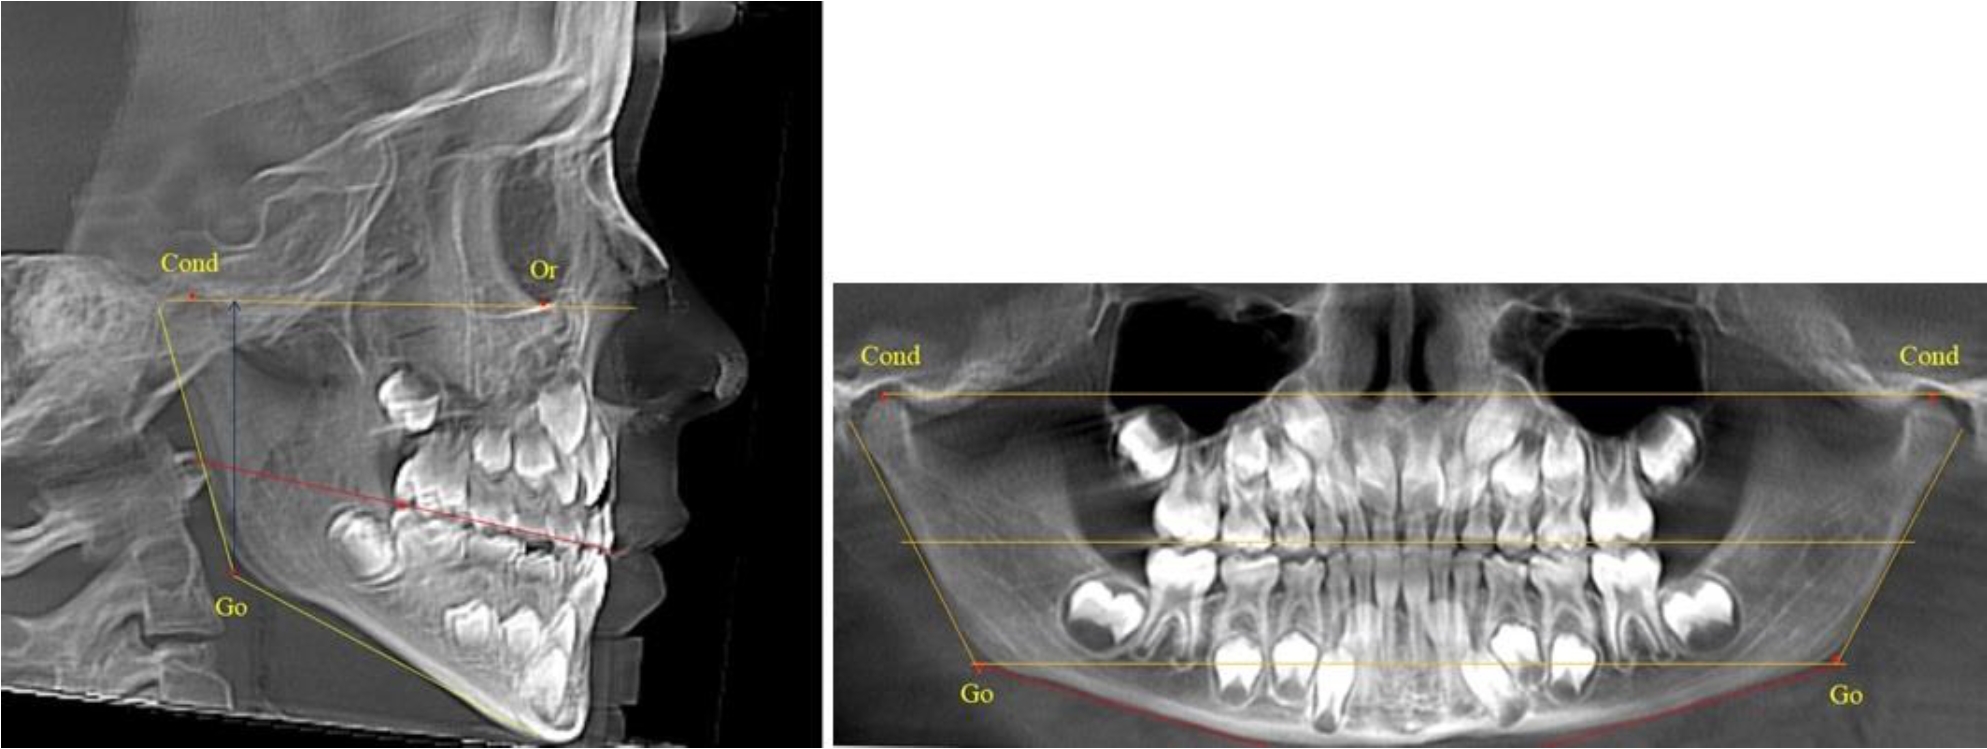

В 3-й группе были проанализированы 9 телерентгенограмм и 9 ортопантомограмм, что составило (8,49 ± 2,71) % от числа изученных рентгенограмм (рис. 3).

Рис. 3. ТРГ и ОПТГ пациента после смены молочных резцов

На всех рентгенограммах произошла смена молочных резцов постоянными. Окклюзионная линия делила ветвь на два отдела.

Высота ветви у детей у детей 3-й группы составляла (51,07 ± 2,72) мм, что было достоверно больше, чем у детей 1-й группы (р ˂ 0,05). При этом высота верхней окклюзионно-суставной части была (29,06 ± 1,44) мм, а нижней – (22,01 ± 1,59) мм. Высота верхней части была больше нижней, что и определяло особенности соразмерности частей ветви нижней челюсти в анализируемый возрастной период.

Относительные показатели соразмерности частей ветви нижней челюсти показали, что отношение высоты верхней части ветви к нижней в среднем составляло 1,32 ± 0,14. Отношение общей высоты ветви к верхней ее части составляло 1,75 ± 0,12, а отношение общей высоты ветви к нижней ее части было 2,32 ± 0,17, что и определяло особенности соразмерности частей ветви нижней челюсти в анализируемый возрастной период.